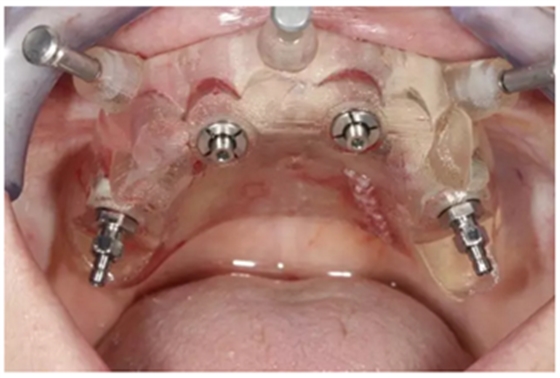

通過固位釘固定上頜NobelGuide外科導(dǎo)板和第一枚已植入的植體和導(dǎo)板基臺。

4枚NobelReplace CC RP4.3植體(11.5mm 軸向植體和13mm 傾斜植體)已植入完成:前牙區(qū)植體上裝配的是導(dǎo)板基臺,后牙傾斜植體上裝配的是內(nèi)錐形連接的引導(dǎo)式持釘器。